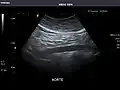

Aorta: Visualized portions normal in caliber, 16 x 15 mm.

Aorta -